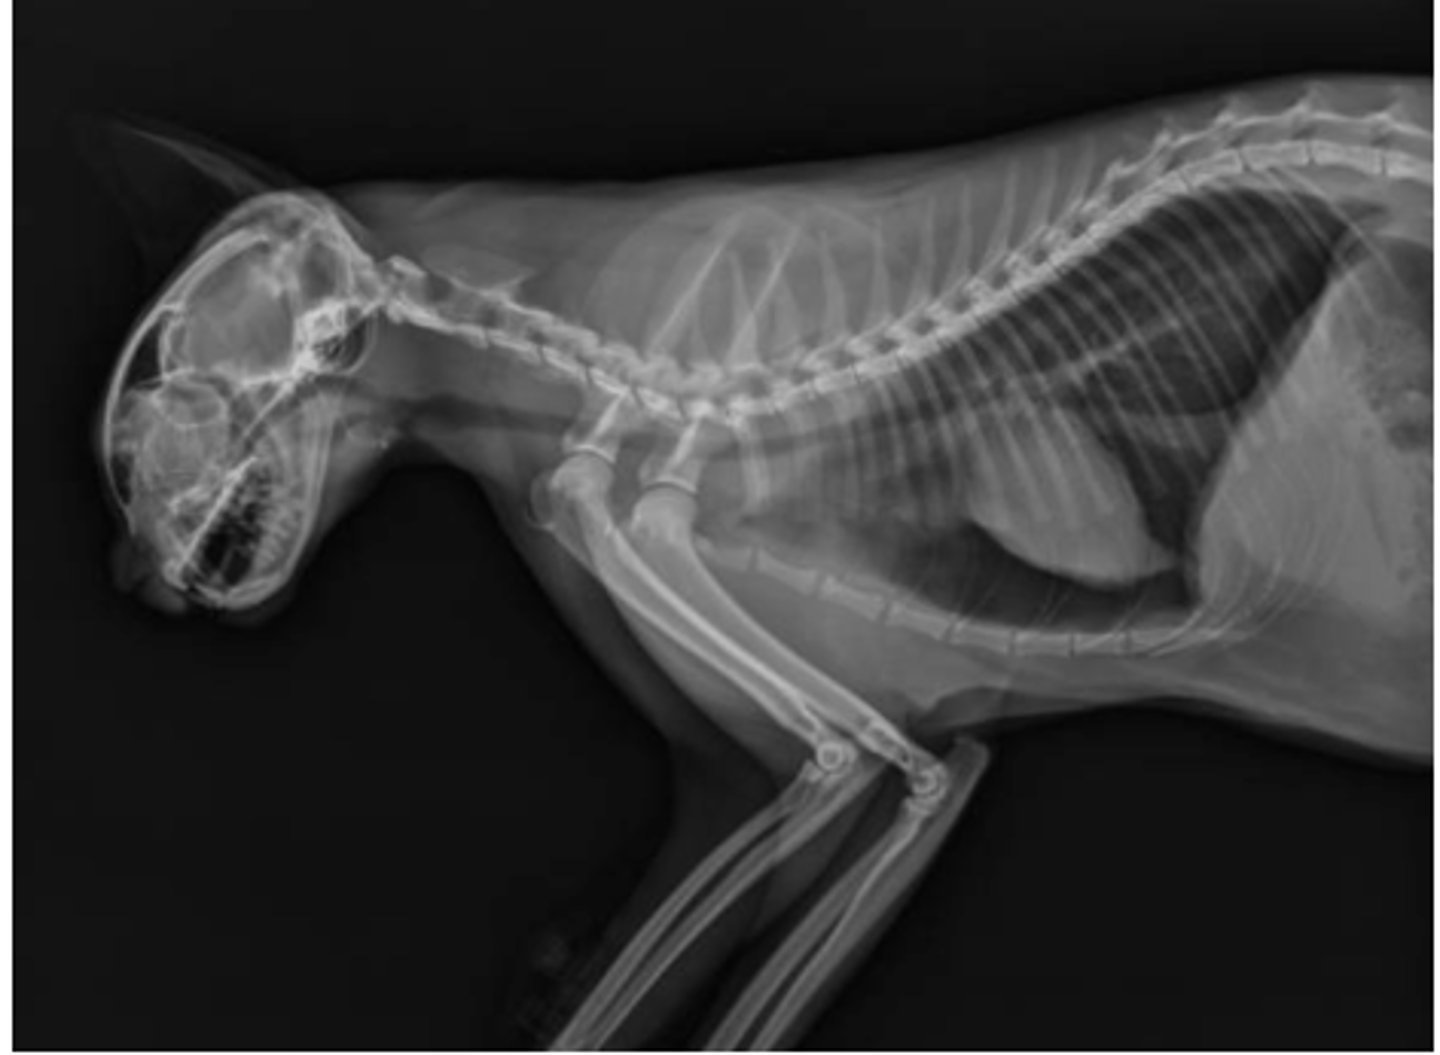

Center in on thorax and stretch thoracic limbs cranially

What changes would you make to this radiograph of a feline?